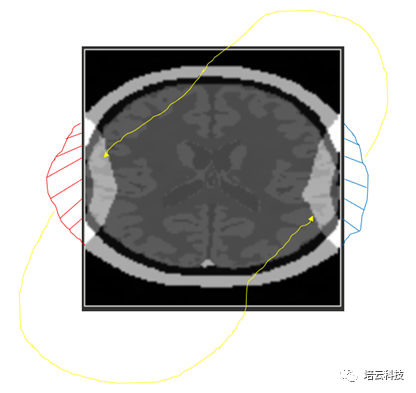

仔细观察会发现,其卷褶是对侧进行的(图4所示),即左侧溢出的部分会卷褶到右侧,而右侧溢出的部分卷褶到左侧。同理,上下侧卷褶也是同样的。那么为什么必须是对侧卷褶的?很欣慰有好学的学子线上提出这个值得深究的问题。

图4 卷褶伪影的对侧卷褶特点

基于MRI图像是频率分布的基本概念,结合离散采样会导致频谱周期延拓的性质,可知:当样品的信号频率范围大于采样带宽时,离散采样后的周期延拓,使得高频部分卷入了低频一侧,而低频部分卷入了高频一侧。由于MRI图像的频率和空间是一致(即通过系数k实现比例变换)的,因此体现出左侧溢出部分卷褶到右侧,而右侧溢出部分卷褶到左侧的表现。